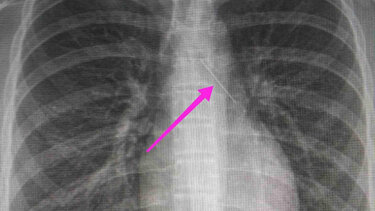

Σύμφωνα με ανάρτηση του νοσοκομείου στα μέσα κοινωνικής δικτύωσης, από την απεικονιστική διερεύνηση που πραγματοποιήθηκε με ακτινογραφία θώρακος αρχικά και ακολούθως με αξονική τομογραφία θώρακος, διαπιστώθηκε η ύπαρξη αιχμηρού μεταλλικού ξένου σώματος στην αναπνευστική οδό (αριστερός κύριος βρόγχος) και όχι στην πεπτική οδό.

“Χθες 30/1/2022 στις 16:00 στο Τ.Ε.Π. του ΓΝΘ Ιπποκράτειο, προσήλθε ανήλικη συνοδευόμενη από τους γονείς της, μετά από αναφερόμενη κατάποση ξένου σώματος (καρφίτσα). Από την απεικονιστική διερεύνηση που πραγματοποιήθηκε με ακτινογραφία θώρακος αρχικά και ακολούθως με αξονική τομογραφία θώρακος, διαπιστώθηκε η ύπαρξη αιχμηρού μεταλλικού ξένου σώματος στην αναπνευστική οδό (αριστερός κύριος βρόγχος) και όχι στην πεπτική οδό.